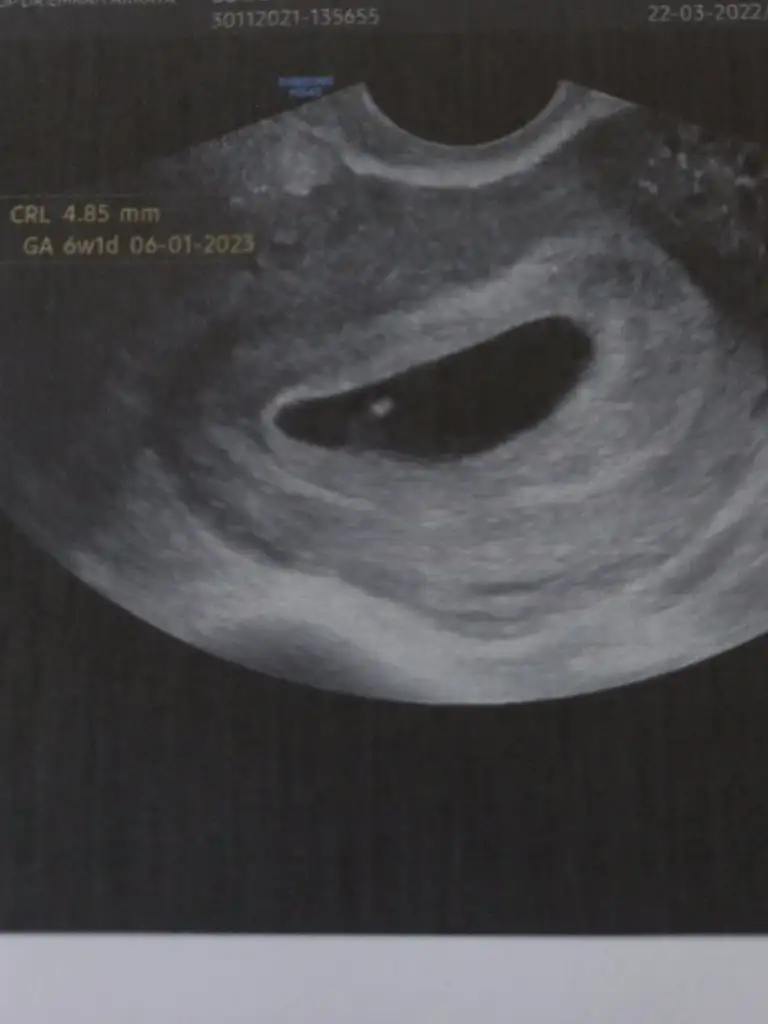

Benim adetime 5 gün var ve kaset testte bu şekilde çıktı. Birazdan kan tahlili yaptırmaya gideceğim.

İnşallah bende aranıza katılabilirim. Daha önceden 2 kaybım var. İnşallah güzel haberler ile dönerim ve test beni yanıltmıyordur.Eki Görüntüle 3065312